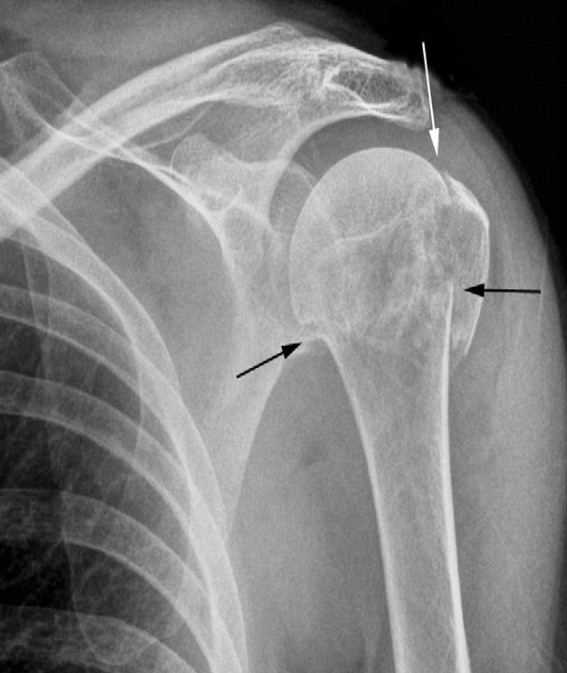

- Plain X-ray

- Electric shock or epileptic seizure

- ‘lightbulb’ appearance of the humeral head.

- Posterior dislocation of the shoulder

Fracture of the neck of the humerus (black arrows)

The greater tuberosity is also fractured (white arrow)